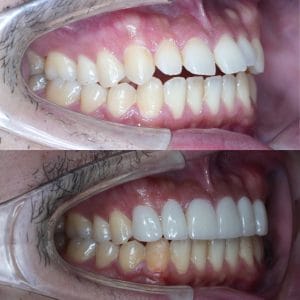

Case030

他院で実施したセラミック矯正の再治療を希望された患者様の症例です。

■色をもっと透明感のある白にしたい。

→当院自慢の一流技工士による最高品質ジルコニアセラミックにて透明感のある白へ

実際は写真でみるよりももっと透明感があります。

■前歯の歯の長さが違うのを治したい

→レーザーによる歯肉整形術で均等な歯の長さへ

■出っ歯に作られている前歯を引っ込めたい

→施術を担当した理事長の形成により、内側に入れるデザインにして洗練された口元へ。これによりEラインも整います。

■歪んだ歯並びを綺麗に

→施術を担当した理事長による形成、印象と技工士との連携により綺麗な歯並びへ

■タバコを吸ってた頃のヤニのついた黒くなってしまった歯茎が気になる

→レーザーによるメラニン色素除去でピンク色の歯茎に戻して若々しい印象へ